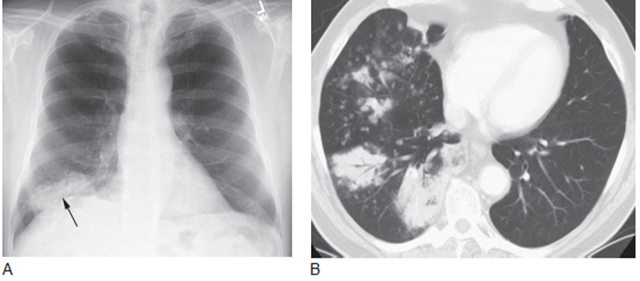

2. 细支气管肺泡癌的实变

40%的细支气管肺泡癌(BAC) 在影像学上表现为肿瘤引起的弥漫性肺浸润,尤其是BAC 的黏液亚型, 大多数BAC 为混合表现。弥漫性BAC 的主要影像学表现如下:

1) 片状、大叶的或弥漫性实变伴空气支气管征(60%)(图13,图14,图15A)。

2) 多发的模糊结节(30%)(图13B,图15B、C)。

3) 片状、大叶的或弥漫性肺磨玻璃样致密影(10%)。

CT 上BAC 患者的实变区呈低密度影,这很大程度上是肿瘤产生的水样液体和黏液所致。如果行对比增强,强化的肺血管在实变的区域内可见,称为“CT 血管造影征”,描述了实变肺的低密度改变。CT 血管造影征是BAC 的典型表现,看到这一征象应想到BAC。

BAC 的模糊结节代表局灶性实变,具有典型的气腔结节特征(图13B,图15B)。直径常在5mm ~ 1cm,也可更大。在CT 上呈小叶中心分布。

图13 弥漫性细支气管肺泡癌

A. 胸片显示右肺基底部的实变( 箭头);B.5mm 层厚的CT 显示多个区域的实变,含有空气支气管征,多发的边界不清的结节,这些结节呈小叶中央分布,代表气腔或腺泡结节,在弥漫性细支气管肺泡癌中很常见

图14 弥漫性细支气管肺泡癌侵犯两上叶,伴实变和空气支气管征

图15 弥漫性细支气管肺泡癌(BAC)

A. 伴双肺实变的BAC;B. 伴两肺模糊小结节;C. 同一患者高分辨率CT 显示弥漫分布的小结节